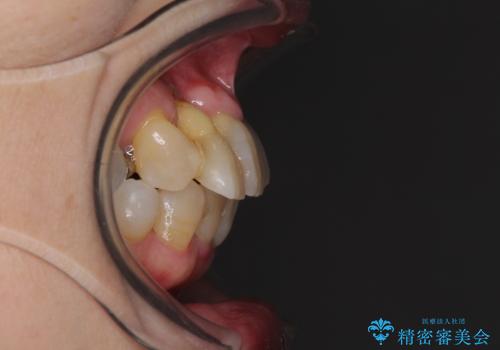

- 歯の欠損や歯肉からの出血などを気にして来院された患者様です。

診査の結果、歯周病であることが分かり、抜歯が必要な歯も見受けられました。

骨造成やインプラント、歯周外科、歯肉移植、矯正など、多くの処置を組み合わせて治療を行うこととしました。